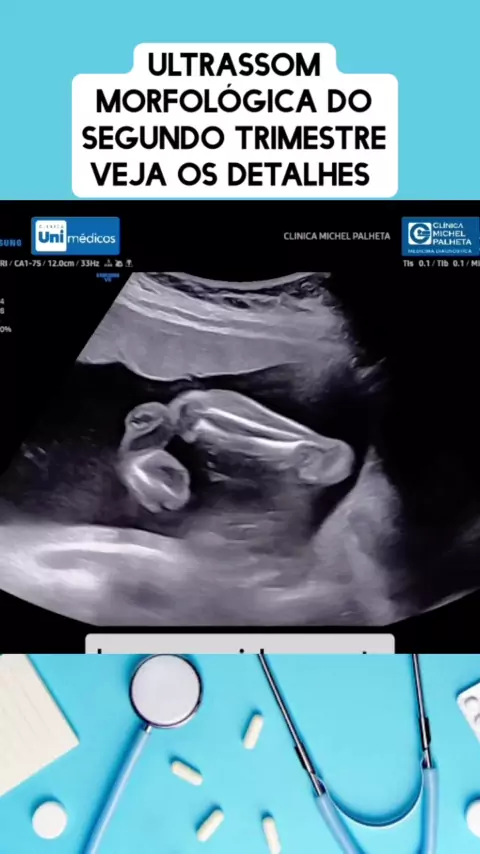

detalhes da ultrassom obstétrica #medico #medicina #Saúde #viraliza